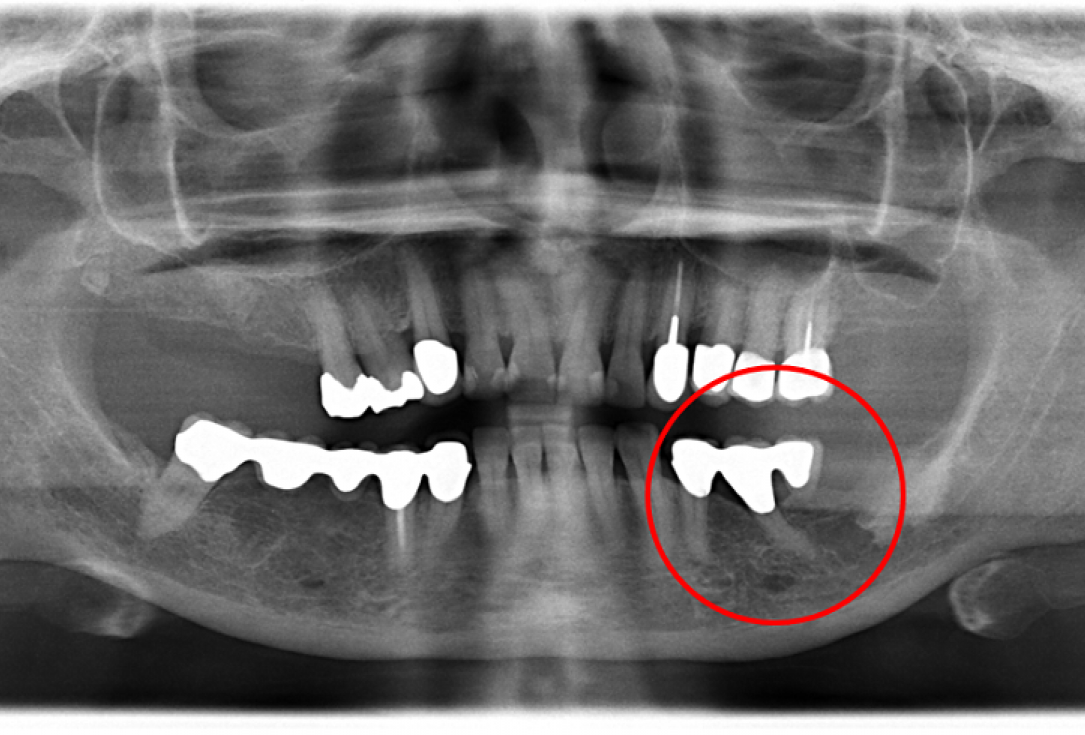

Pre-operative OPG shows deep vertical intrabony defects on the distal aspects of teeth 13 and 14.